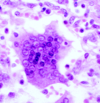

What organism is seen in the photo?

Toxoplasma gondii

The latent form is represented by slow-growing protozoa forms called bradyzoites encased in cysts with a cyst wall. Multiple basophilic dot-like parasites can be seen in cysts